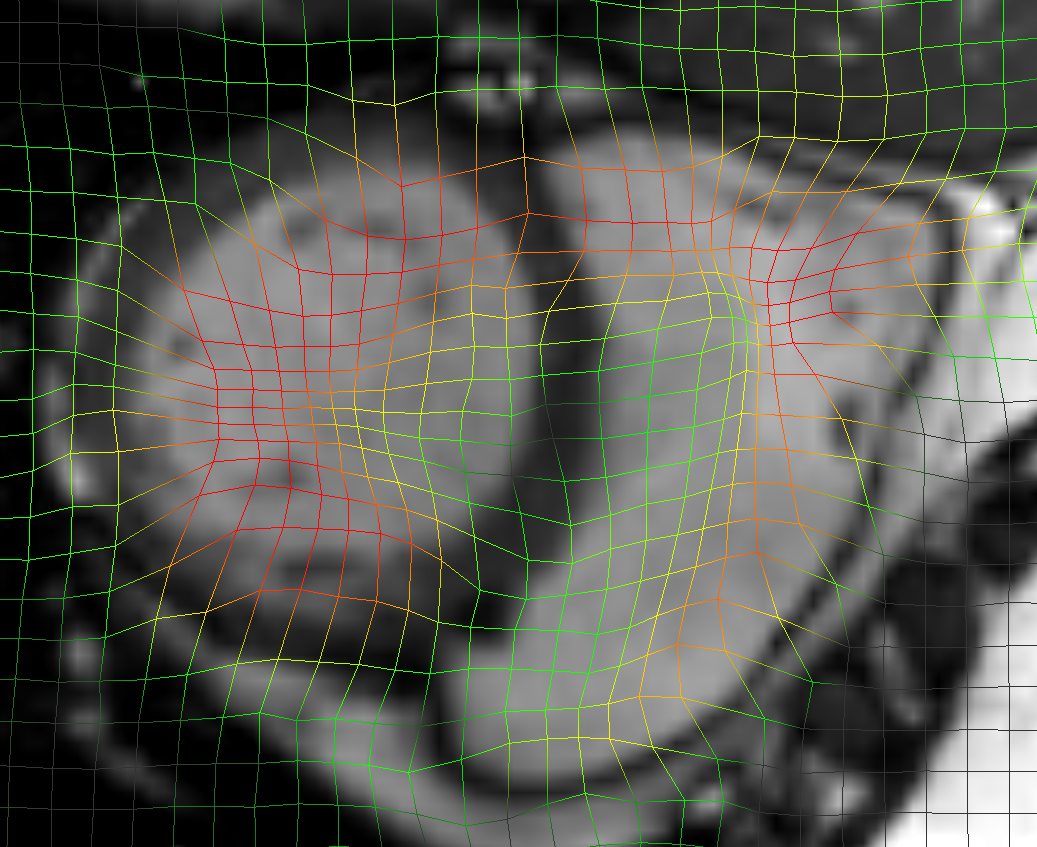

The initial average landmark distance between consecutive phase images was 2.25 1.55 mm for the Popi datasets and 2.19 2.02 mm for the DirLab datasets. The proposed registration algorithm could decrease the average distance to 1.24 0.90 mm and 1.54 1.31 mm, respectively. For a comparison with existing 4D registration methods we applied the publicly available method by [23] to the respiratory datasets and achieved average registration errors similar to the ones of our method: 1.56 1.42 mm for the DirLab and 1.11 0.87 mm for the Popi datasets. The construction of trajectories for voxels requires the combination of all DVF of a 4D dataset. As a consequence the registration error at the start of a trajectory gets propagated over time and increases or decreases with the combination of the different DVF. In Fig. 4 the error evolution is visualised for the three test datasets. At the beginning the mean registration error is 1.54 mm for the DirLab datasets and 1.24 mm for the Popi datasets. The error then increases to a mean of 2.58 mm for DirLab and 2.07 mm for Popi in the middle of the periodic motion. In the end of the breathing cycle the error falls to an error around 1 mm for both datasets. A similar error propagation pattern could be measured for the Sunnybrook datasets. For the Sunnybrook datasets segmentations are only available for the extreme phases, which allows only four comparisons per dataset. When starting with the end-diastolic phase a comparison in the middle of the cyclic motion to the end-systolic segmentation and in the end of the cycle motion to the original end-diastolic segmentation is possible. The same applies when starting with the end-systolic segmentation. In Fig. 4 the red dots indicate the measured DSC overlap, the red dotted line was fitted to the dots and estimates the DSC overlap for phase images without a segmentation available. Compared to a direct registration of the maximum exhale and inhale phases the registration error increased on average by 0.48 mm with the combination of the DVF. The average registration error for the extreme phases in the Popi dataset increased from 1.46 1.59 mm to 1.98 1.56 mm when we registered the whole 4D dataset instead of the two extreme phases solely. The same analysis reported an increase from 1.83 2.35 mm to 2.54 2.01 mm for the DirLab images and and decrease in the DSC from 0.86 0.10 to 0.79 0.14 for the Sunnybrook data. The DVF of the 4D evaluation showed a FoF of 0.02 % and an average Jacobi determinant of 1.00 0.06.

a) DirLab08 deformation grid

for inhale to exhale registration

a) DirLab08 deformation grid

for inhale to exhale registration